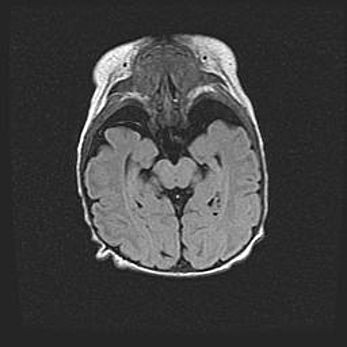

Лейкомаляция с кистозно-глиозной дегенерацией головного мозга.

Возраст: 2 месяца 25 дней

Вес: 6400 г

Окружность головы: 40 см

Срок гестации: 41 неделя

Лейкомаляцию относят к ишемически-гипоксическим повреждениям головного мозга, диагностируемым у новорожденных. При лейкомаляции в головном мозге обнаруживают очаги некроза, возникшие после тяжелой гипоксии и нарушения кровотока. В процессе морфогенеза очаги проходят три стадии: 1) развития некроза, 2) резорбции и 3) формирования глиозного рубца или кисты. Перивентрикулярная лейкомаляция (ПЛ) встречается примерно в 12% случаев среди новорожденных, обычно – у недоношенных детей, причем, частота ее зависит от массы, с которой младенец появился на свет. Наибольшее число малышей страдает лейкомаляцией, если масса при рождении 1500-2500 г.